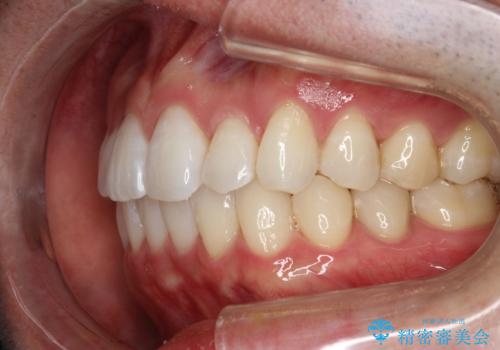

フルリンガル矯正 非抜歯でガタつきを整える

- フルリンガルワイヤーによる非抜歯治療を計画しました。

フルリンガルは違和感も強く操作も煩雑になるため、あまりおすすめはしていませんが、お仕事の都合などでどうしても装置を付けられない&マウスピースを管理することができない、場合はやむなく選択することもあります。